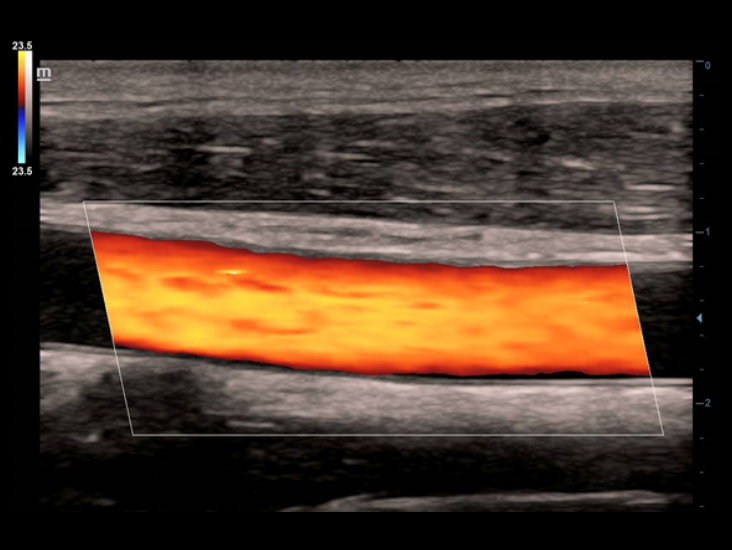

Transduser ComboWave

Dibandingkan dengan transduser tradisional, transduser ComboWave memanfaatkan tipe baru bahan piezoelektrik komposit untuk meningkatkan spektrum akustik dan mengurangi impedansi akustik. Dengan integrasi yang lebih erat dengan teknologi 3T unik dari Mindray, transduser linier ComboWave memungkinkan kinerja luar biasa dengan resolusi gambar yang tinggi dan uniformitas di tiroid, payudara, pembuluh darah, dan lainnya.

Smart Track

Smart Track menyediakan optimasi yang cepat dan cerdas untuk pencitraan vaskular dengan operasi satu sentuhan yang sederhana. Alat ini bisa mengoptimalkan spektrum Warna, Daya, dan PW dengan melakukan pelacakan mandiri dan mengurangi langkah-langkah yang menghabiskan waktu. Oleh karena itu, alur kerja pemeriksaan vaskular disederhanakan dengan tampilan yang optimal.